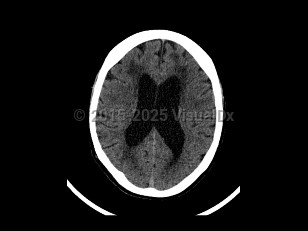

Normal pressure hydrocephalus (NPH) is a common neurologic disorder resulting in slowly progressive gait abnormalities, cognitive deterioration, and urinary incontinence.

The syndrome is often divided into 2 groups, idiopathic and secondary, based on etiology. Idiopathic NPH is thought to occur due to increased resistance to cerebrospinal fluid (CSF) absorption, leading to temporary elevations in intracranial pressure and mechanical compression of structures adjacent to the ventricles. However, the underlying etiology of idiopathic NPH has not yet been identified. Secondary causes of NPH include the sequelae of brain infections such as meningitis, trauma, or subarachnoid hemorrhage. This article will focus on the diagnosis, evaluation, and treatment of idiopathic NPH.

Gait and balance dysfunction typically develop early in the course of NPH, whereas cognitive symptoms and incontinence usually appear as the disease progresses. The typical gait abnormality in NPH is a broad-based, slow, short-stepped, "stuck to the floor" or "magnetic" movement. Postural stability is usually impaired, and a history of falls may be reported. The cognitive deficits are typically impairments in attention, psychomotor speed, and executive dysfunction. Patients with more advanced NPH can develop generalized cognitive dysfunction. Disturbances of bladder function in NPH result from detrusor hyperactivity secondary to a loss of central inhibitory control. Increased urinary frequency and urgency and subsequent incontinence can develop.